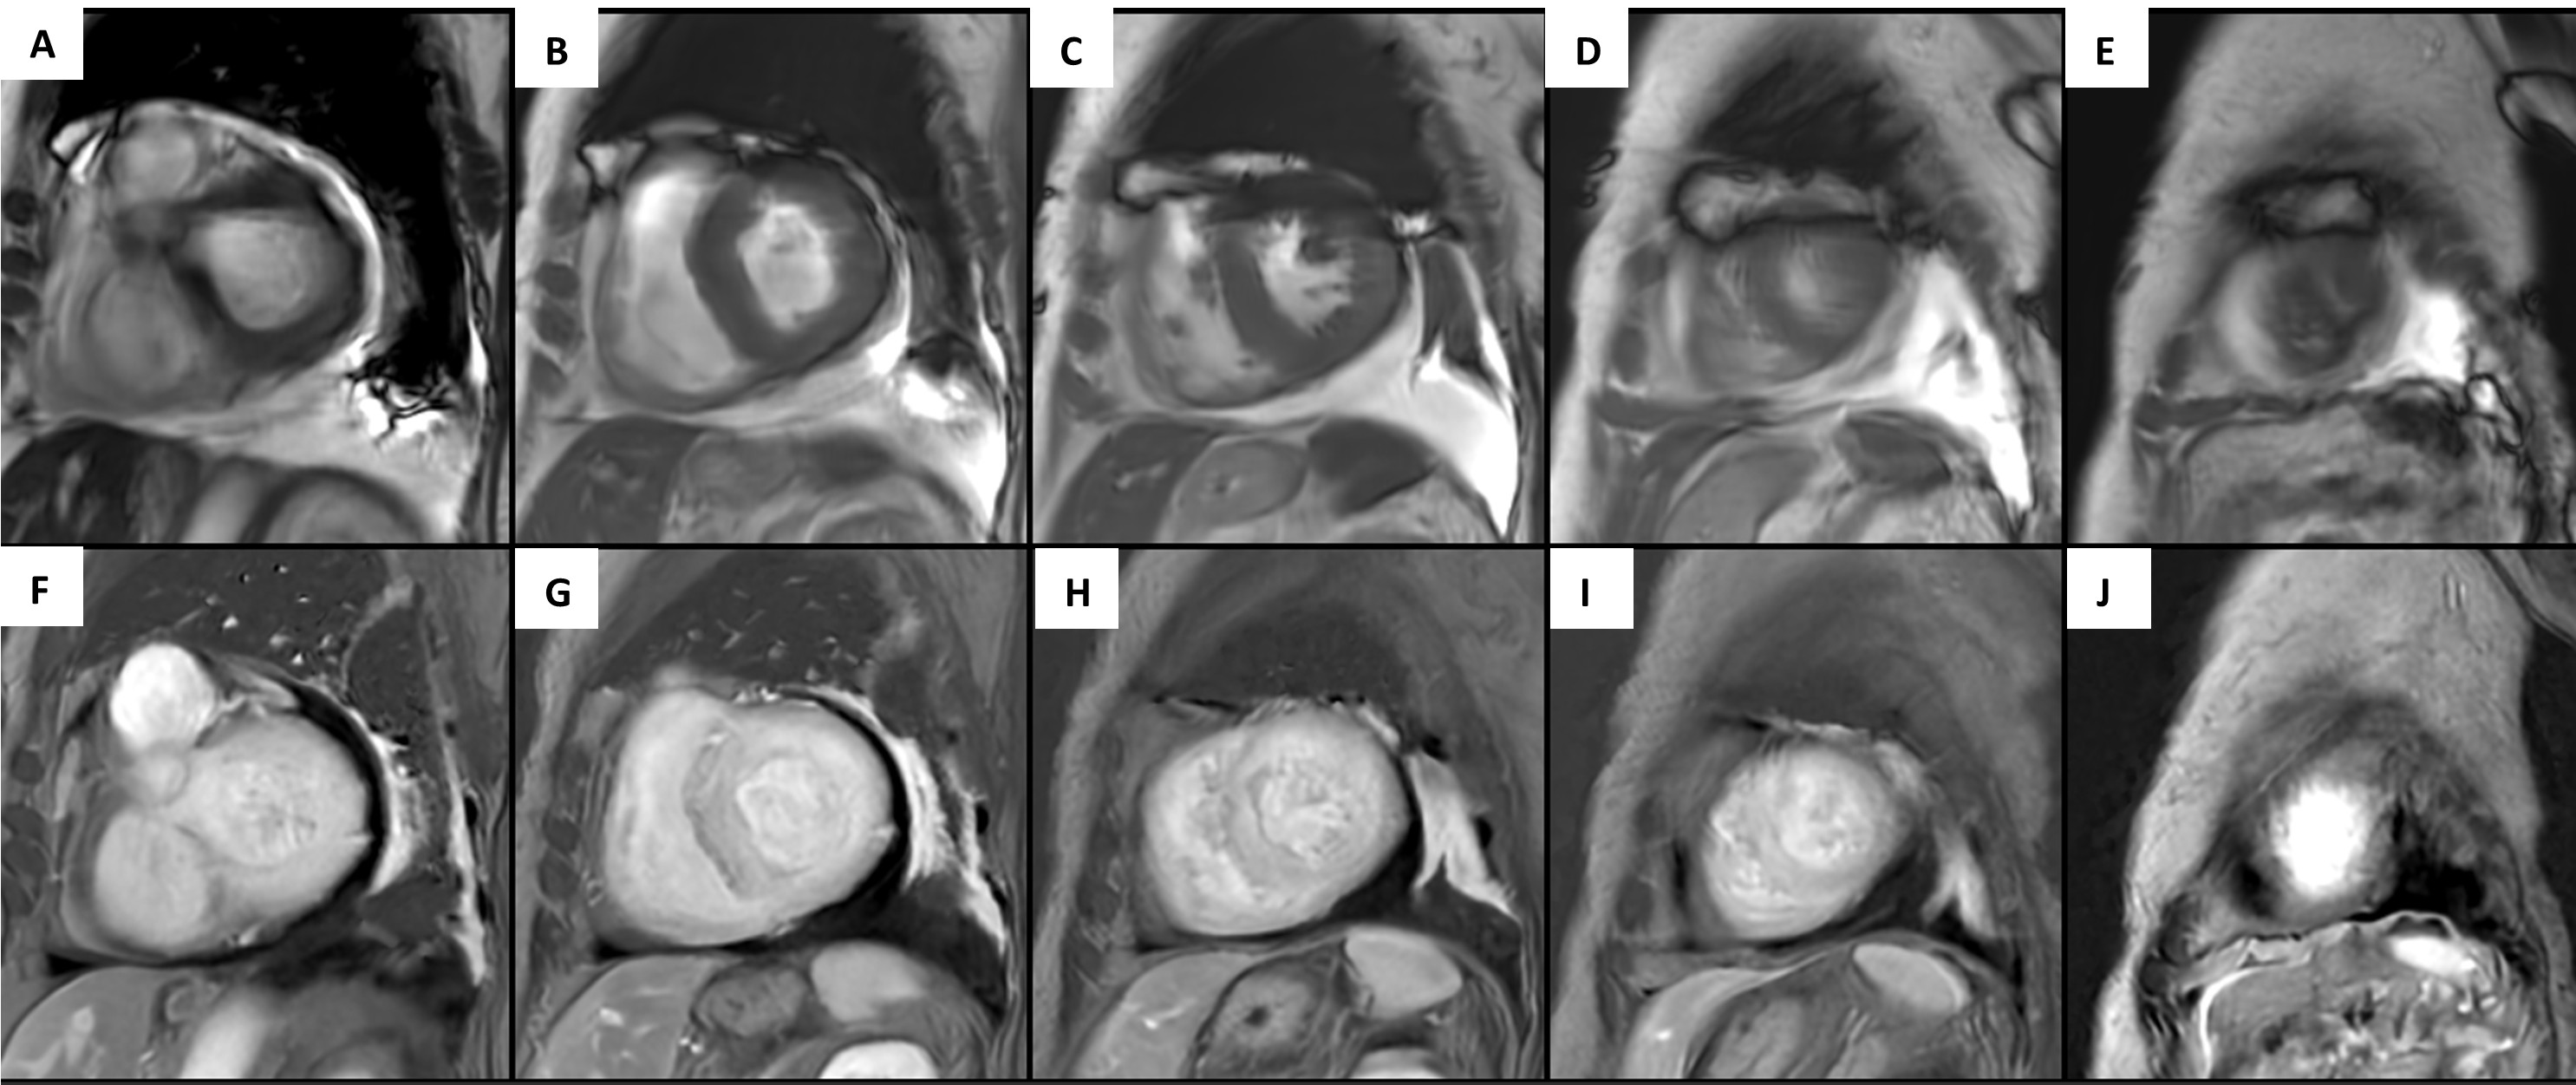

Fig 2. SSFP cine short axis images in end diastole demonstrating significant LV hypertrophy of the (A) (B) LV base, (C) LV mid cavity, and (D) (E) LV apex. The second row of images demonstrate short axis views with the presence of diffuse late gadolinium in the (F) (G) LV base, (H) LV mid cavity, and (I) (J) LV apex.